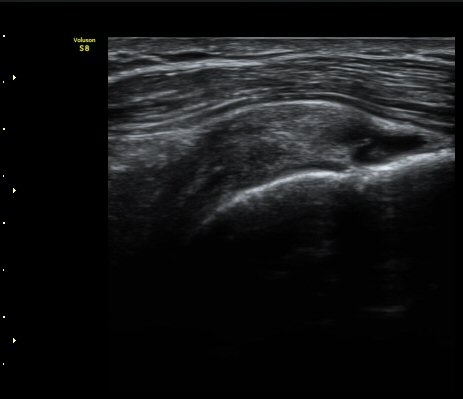

±Ø»ó°Ç Á¾´Ü¸é°Ë»ç»ó ±Ø»ó°Ç ³»Ãø ºÎÂøºÎ¿¡¼­ °Ç¿¬°á¼º ¼Ò½ÇÀÌ °üÂûµÈ´Ù(±×¸² 7, 8).

±Ø»ó°Ç Á¾´Ü¸é°Ë»ç»ó ±Ø»ó°Ç ¼Ò½Ç¿¡ ÀÇÇÑ È¸Àü±Ù°³ °á¼ÕÀÌ °üÂûµÈ´Ù(±×¸² 9, 10).